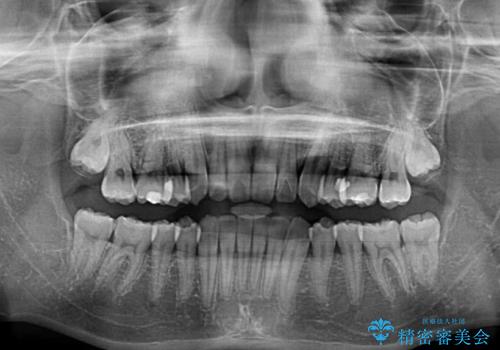

- 奥歯の反対咬合を気にして来院された患者様です。

反対咬合は上顎骨の幅が下顎骨よりも小さいことが原因なので、拡大装置により骨幅を広げて上下関係を改善し、その後インビザラインにて歯並びを整えることとしました。

反対咬合が改善され、食いしばり癖もなくなり、顎関節の負担が軽減されました。

上顎骨を拡大したことで前歯に隙間ができ、1ヶ月ほど恥ずかしい時期がありましたが、しっかりとした咬み合わせに仕上がり、患者様には大変満足していただきました。